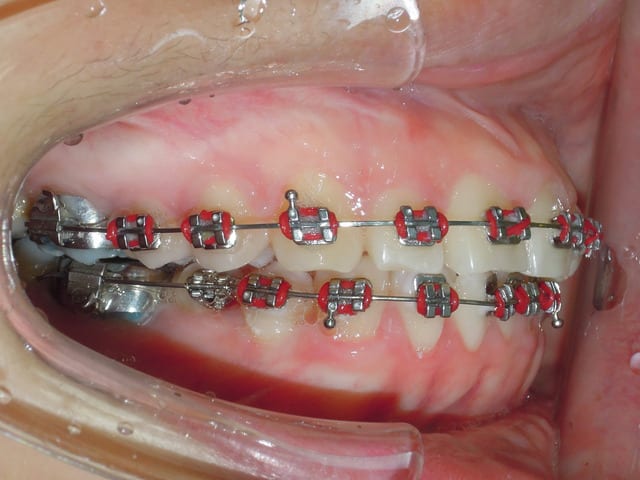

Quand soudain ..

Suite a un problème d'emplois du temps la patient n'a pas pus venir pendant deux mois, a sont retour nous avons la situation suivant .

- open bite

- over jet

La question est donc เกิดอะไรขึ้น